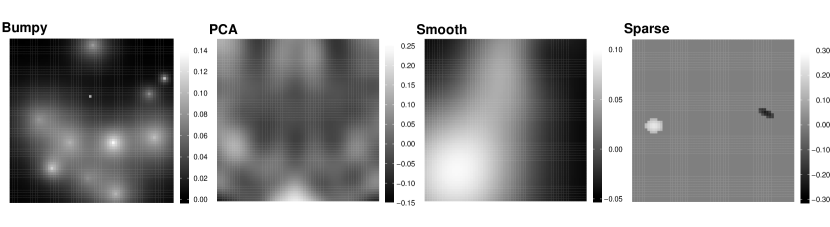

We consider four different coefficient images that reflect the main assumptions in the models (see Fig. 2):

-

•

bumpy Reiss et al., (2015), an image with some high-peaked, clearly defined “bumps”. It is a two-dimensional version of the bump function Donoho and Johnstone, (1994) which has become a common benchmark for one-dimensional wavelet models. It is thus expected that the wavelet-based methods should be the most suitable ones for estimation.

pca, an image constructed as a linear combination of the first principal components of the image covariates found by the rank-one based method Allen, (2013) with coefficients . Obviously, the principal component based method should work very well in this case.

smooth, a smooth image which corresponds to the smoothness assumption made in the spline-based models and for the Bayesian models using Gaussian Markov random fields. It is constructed as a mixture of three 2D normal densities.

sparse, an image that is mostly zero with two small, smooth spikes Goldsmith et al., (2014). This image corresponds to the assumption made for the SparseGMRF model.